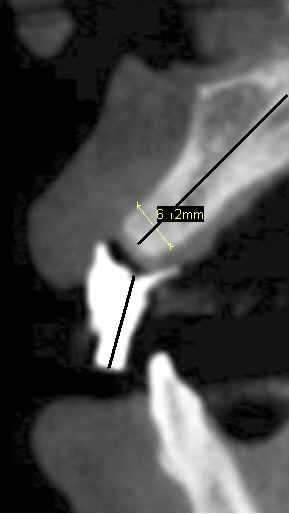

Fig.7 (magnification): the long axes of the drill sleeve for #8 and of the alveolar ridge are not aligned.  The width of the ridge is 6.12mm.  Back to main text